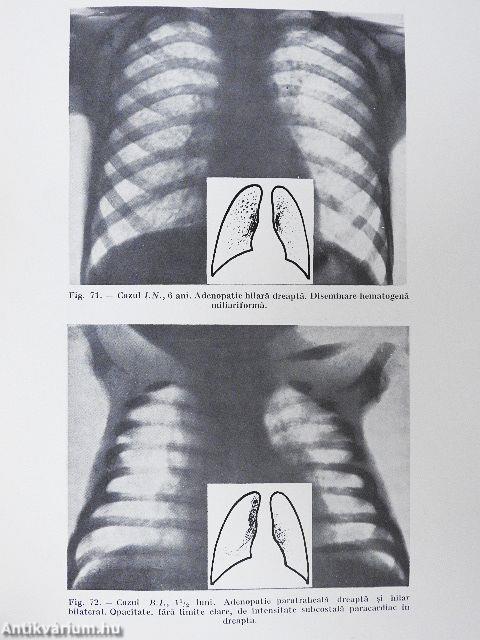

| Megjegyzés: | Fekete-fehér fotókkal, ábrákkal. |